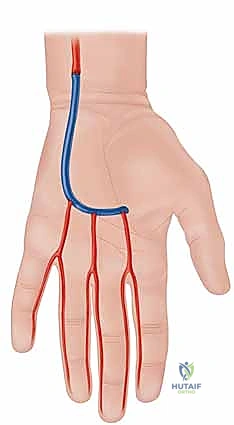

Conversely, vaso-occlusive disorders manifest as a critical reduction in the cross-sectional area of the vessel lumen. This mechanical obstruction can be the sequela of acute thrombosis, distal embolization originating from proximal cardiac or atherosclerotic sources, or focal stenotic lesions inherent to conditions like Buerger’s disease (thromboangiitis obliterans) and hypothenar hammer syndrome. In the latter, repetitive blunt trauma to the hypothenar eminence induces intimal damage, aneurysm formation, and subsequent thrombosis of the ulnar artery, frequently showering microemboli into the digital circulation. Understanding these distinct yet occasionally overlapping pathophysiological mechanisms is absolute prerequisite for selecting the appropriate surgical armamentarium, be it adventitial sympathectomy to relieve spasm, or microvascular bypass and embolectomy to restore luminal patency.

The primary clinical indications include progressive, unrelenting pain at rest, the development of ischemic digital ulcerations, or impending gangrene. In the context of vasospastic disease, a periarterial digital sympathectomy is indicated when symptoms are severe and progressive, provided there is no major proximal occlusion of the radial or ulnar arteries, and adequate distal target vessels (at least three patent common digital arteries) can be visualized angiographically. Conversely, in vaso-occlusive disease—such as an acute embolus or hypothenar hammer syndrome—direct arterial reconstruction, embolectomy, or vein graft bypass is mandated to bridge the occluded segment and restore inline pulsatile flow.

| Hypothenar Hammer Syndrome | Ulnar artery aneurysm, distal microembolization, digital ischemia, claudication of the hand. | Lack of viable distal run-off vessels for bypass; asymptomatic incidental finding. | Extensive proximal atherosclerotic disease precluding adequate inflow. |

| Acute Embolic Event | Sudden onset pallor, pulselessness, pain, paresthesia, paralysis (the 5 Ps) indicating acute limb/digit threat. | Irreversible tissue necrosis/gangrene (requires amputation instead). | Delayed presentation where ischemic time exceeds viability threshold. |

If, during the exploration, an area of fixed occlusion or a thrombosed aneurysm (such as in hypothenar hammer syndrome) is encountered, the procedure transitions from sympathectomy to microvascular reconstruction. The diseased arterial segment is resected until healthy, pulsatile intima is visualized proximally and distally. An autologous reversed saphenous vein graft is harvested, prepared, and interposed into the defect. End-to-end microvascular anastomoses are performed using 8-0 or 9-0 non-absorbable monofilament sutures under the microscope, ensuring precise intimal coaptation to prevent turbulent flow and re-thrombosis.

Modern clinical guidelines, supported by the American Society for Surgery of the Hand (ASSH), emphasize a multidisciplinary, stepwise approach to upper extremity ischemia. Surgery is firmly positioned as a salvage therapy following the exhaustion of advanced pharmacological interventions. For vaso-occlusive diseases, the literature clearly supports aggressive microvascular reconstruction. Studies evaluating the outcomes of vein grafting for hypothenar hammer syndrome demonstrate patency rates exceeding 80% at five years, provided the patient adheres to strict smoking cessation.